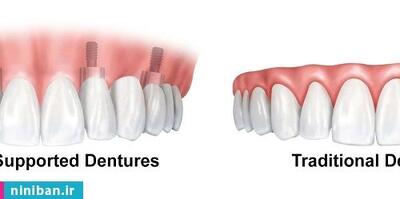

یکی از نوآوریهای اخیر در این زمینه، ایمپلنت دندان دیجیتال است که در کلینیک دندانپزشکی ایثار با استفاده از تکنولوژی پیشرفته انجام میشود. در این مطلب قصد داریم به بررسی هزینه ایمپلنت دندان و مزایای انتخاب ایمپلنت دیجیتال در کلینیک ایثار بپردازیم.

ایمپلنت دیجیتال دندان (Digital implant surgery) از فناوریهای سهبعدی کامپیوتری برای تحلیل وضعیت استخوان فک و موقعیت عصب دندان بهره میبرد. در این روش، برشها به حداقل میرسند که در نتیجه آن، نیاز به بخیه کاهش یافته و فرآیند بهبودی سریعتر انجام میشود. با این تفاسیر معمولا متقاضیان کاشت ایمپلنت این …

ایمپلنت دندان بهعنوان یک راهحل دائمی و موثر برای بازیابی زیبایی و عملکرد دندانها شناخته میشود. این مقاله به بررسی کارکردهای ایمپلنت دندان، مزایا و معایب آن، اهمیت انتخاب متخصص ایمپلنت، و در نهایت، نکات مهمی که باید قبل از انجام این عمل بدانید، میپردازد.

مهمترین عامل در درمان ایمپلنت، مهارت دندانپزشک است. این موضوع نه فقط در مورد طول عمر ایمپلنت، بلکه در مورد پروسه درمان هم بسیار مهم است.

ایمپلنت دندان یکی از پیشرفته ترین و موثرترین روش ها برای جایگزینی دندان های از دست رفته است. این روش با استفاده از پایه های تیتانیومی